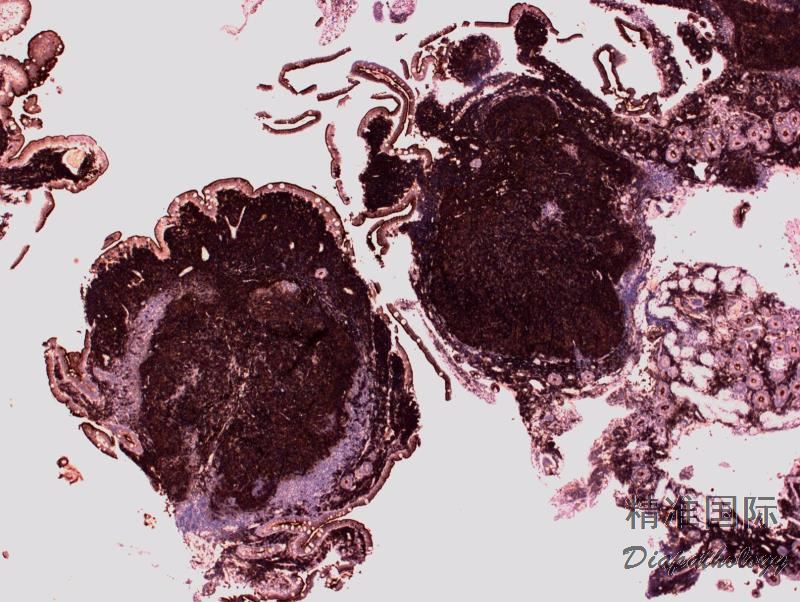

淋巴结正常结构消失,代之以紧密排例、大小和形状一致的不正常滤泡,常累及整个淋巴结或浸润到胞膜外。套区变薄、不完整、消失或极性不在。有的同时存在弥漫浸润区。偶而滤胞呈现出形状不规则或匐行性生长(类似进行性滤胞中心转化, PTGC)。

滤泡由中心细胞和不等数量的中心母细胞组成,两种细胞随机散在分布,极性和“星空”细胞消失。滤泡之间或可见浸润中心细胞。中心细胞:较中心母细胞小,核形不规则成角或有核裂,胞质少。中心母细胞:核圆形或卵圆形,呈空泡状,可见 1 ~ 3 核仁,多靠近核膜。滤泡之间或可见肿瘤细胞侵润,系中心细胞,但胞核相对规则。

免疫表型:表达 B 细胞抗原如 CD20 和 CD19,CD10+,Bcl-6+,Bcl-2+,单克隆轻链。高级别 FL,CD10 阴性相对常见。滤胞间肿瘤细胞(低级别或高级别)常弱表达或不表达 CD10,边缘区分化区域(FL 伴边缘区分化)、骨髓或外周血中的肿瘤细胞也常不表达 CD10。滤胞间区的肿瘤细胞表达 Bcl-6 也减弱。